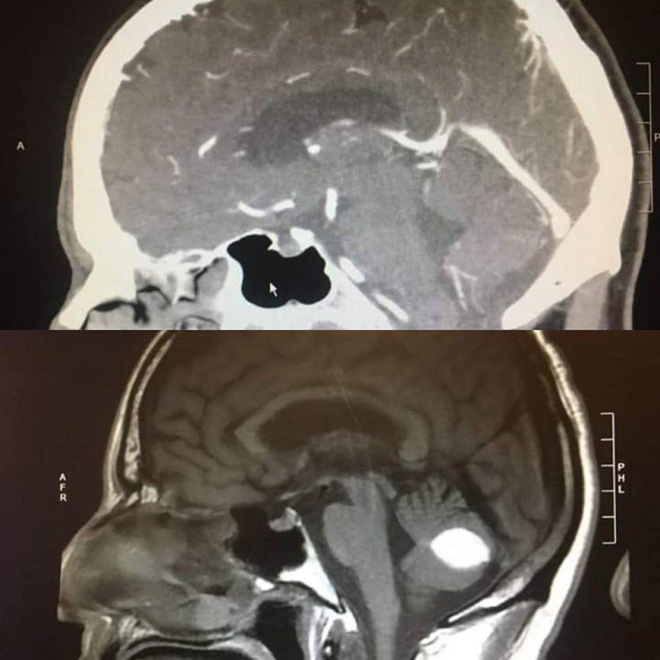

Hình ảnh não ông Paul khi mới phát hiện khối u và trước thời điểm dự định phẫu thuật 1 ngày.

Thế rồi, trước ngày lên bàn mổ 1 ngày, ông Paul đến bệnh viện để chụp cắt lớp lần nữa thì bác sĩ phát hiện ra khối u đã tự nhiên biến mất, não của Paul hoàn toàn bình thường.

Tấm phim chụp vẫn còn đó, đốm trắng trong não Paul là hoàn toàn có thật nhưng không ai hiểu tại sao nó lại biến mất bí ẩn như vậy.